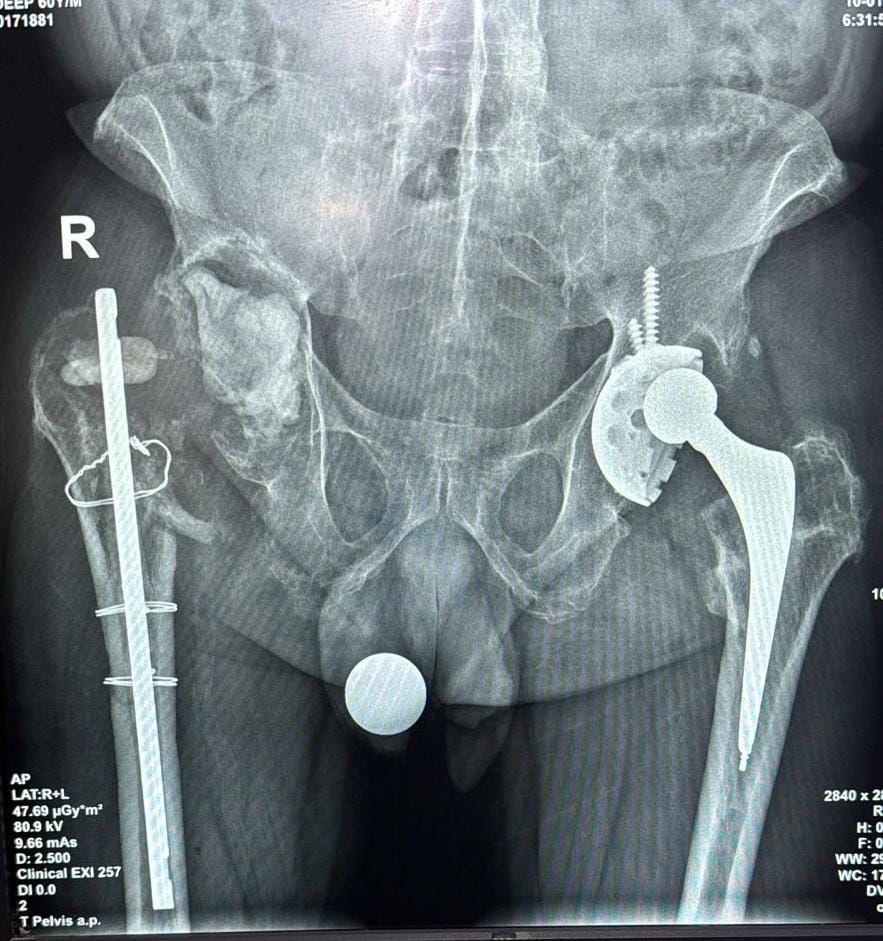

बकौल, संदीप शर्मा उन्होंने अपने उपचार के लिए गतवर्ष 2024 में एम्स AIIMS, दिल्ली में उपचार हेतु परामर्श लिया, जहां सर्जरी की प्रक्रिया शुरू की गई। मगर संक्रमण के चलते सर्जरी अधूरी रह गई और चिकित्सकों ने अस्थायी समाधान के तौर पर एक सीमेंट स्पेसर और स्टेबलाइजिंग नेल का उपयोग किया।

यहां विशेषज्ञ डॉक्टरों की टीम द्वारा तमाम जरूरी जांच के बाद यह स्पष्ट हुआ कि उनके कुल्हे की हड्डी में एक बहुत बड़ा दोष (बोनी डिफेक्ट) है, जिसे सामान्य इम्प्लांट्स से ठीक कर पाना संभव नहीं था। ऐसे में मरीज के लिए विशेषरूप से डिजाइन किया गया 3D प्रिंटेड कस्टमाइज्ड इम्प्लांट तैयार कराया गया।

बीते फरवरी माह के अंतिम सप्ताह में प्रोफेसर रूप भूषण कालिया के मार्गदर्शन में ऑर्थोपेडिक्स विभाग की टीम द्वारा 8 घंटे में यह जटिल सर्जरी को सफलतापूर्वक अंजाम दिया गया। डॉ. रूप भूषण कालिया के अनुसार इस प्रक्रिया में पहले से डाले गए सीमेंट स्पेसर और नेल को हटाकर 3D प्रिंटेड कस्टम इम्प्लांट को प्रत्यारोपित किया गया। राज्य में हुई यह अपनी तरह की पहली जटिल सर्जरी के लिए सहयोगी एनेस्थीसिया टीम का नेतृत्व डॉ. भावना गुप्ता ने किया।